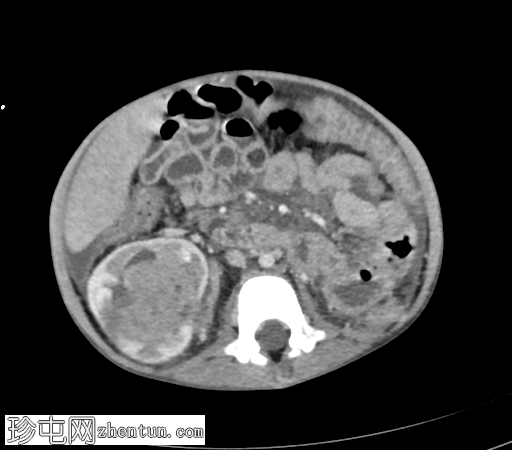

冠状位增强扫描(门静脉期)

右肾极间区可见一巨大异质性肿块,伴坏死区域。

病灶延伸至扩张的右肾静脉、右下腔静脉和右心房。

轻至中度腹水。

可见亚厘米级腹主动脉旁淋巴结。

右侧少量胸腔积液,右下叶可见一小块强化胸膜下结节。

影像学特征提示右肾母细胞瘤(Wilms瘤),伴肿瘤血栓形成至下腔静脉和右心房。